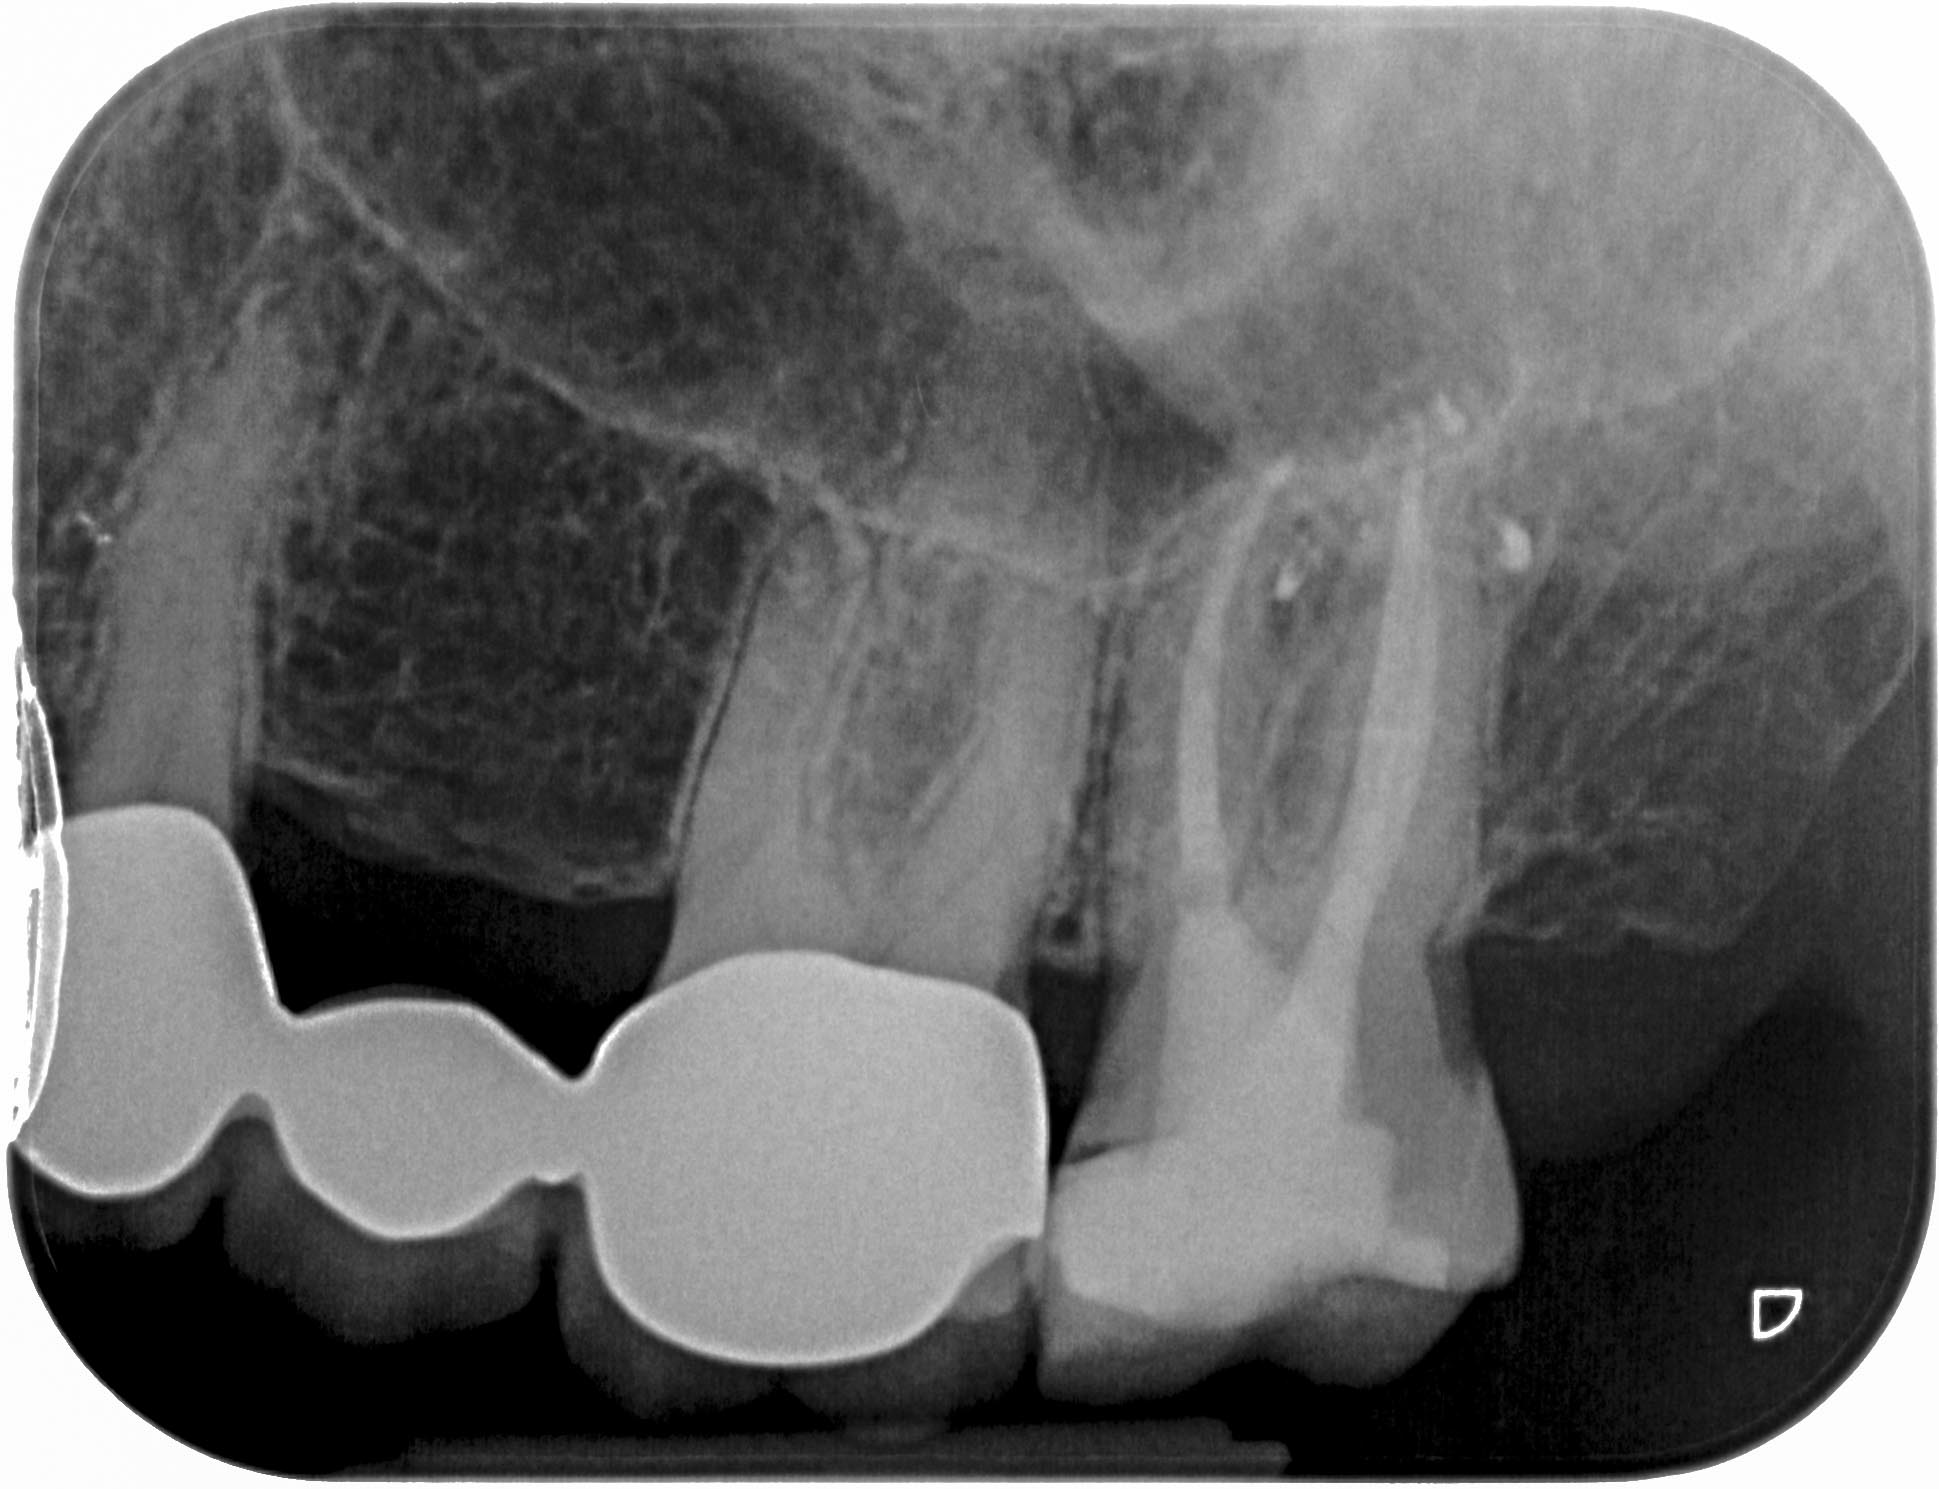

SE_27-6 Veröffentlicht 4. Mai 2014 am 1939 × 1489 in Massive apikale Aufhellung an Zahn 27 im Recall WF- Kontrolle 2 Jahre post WF